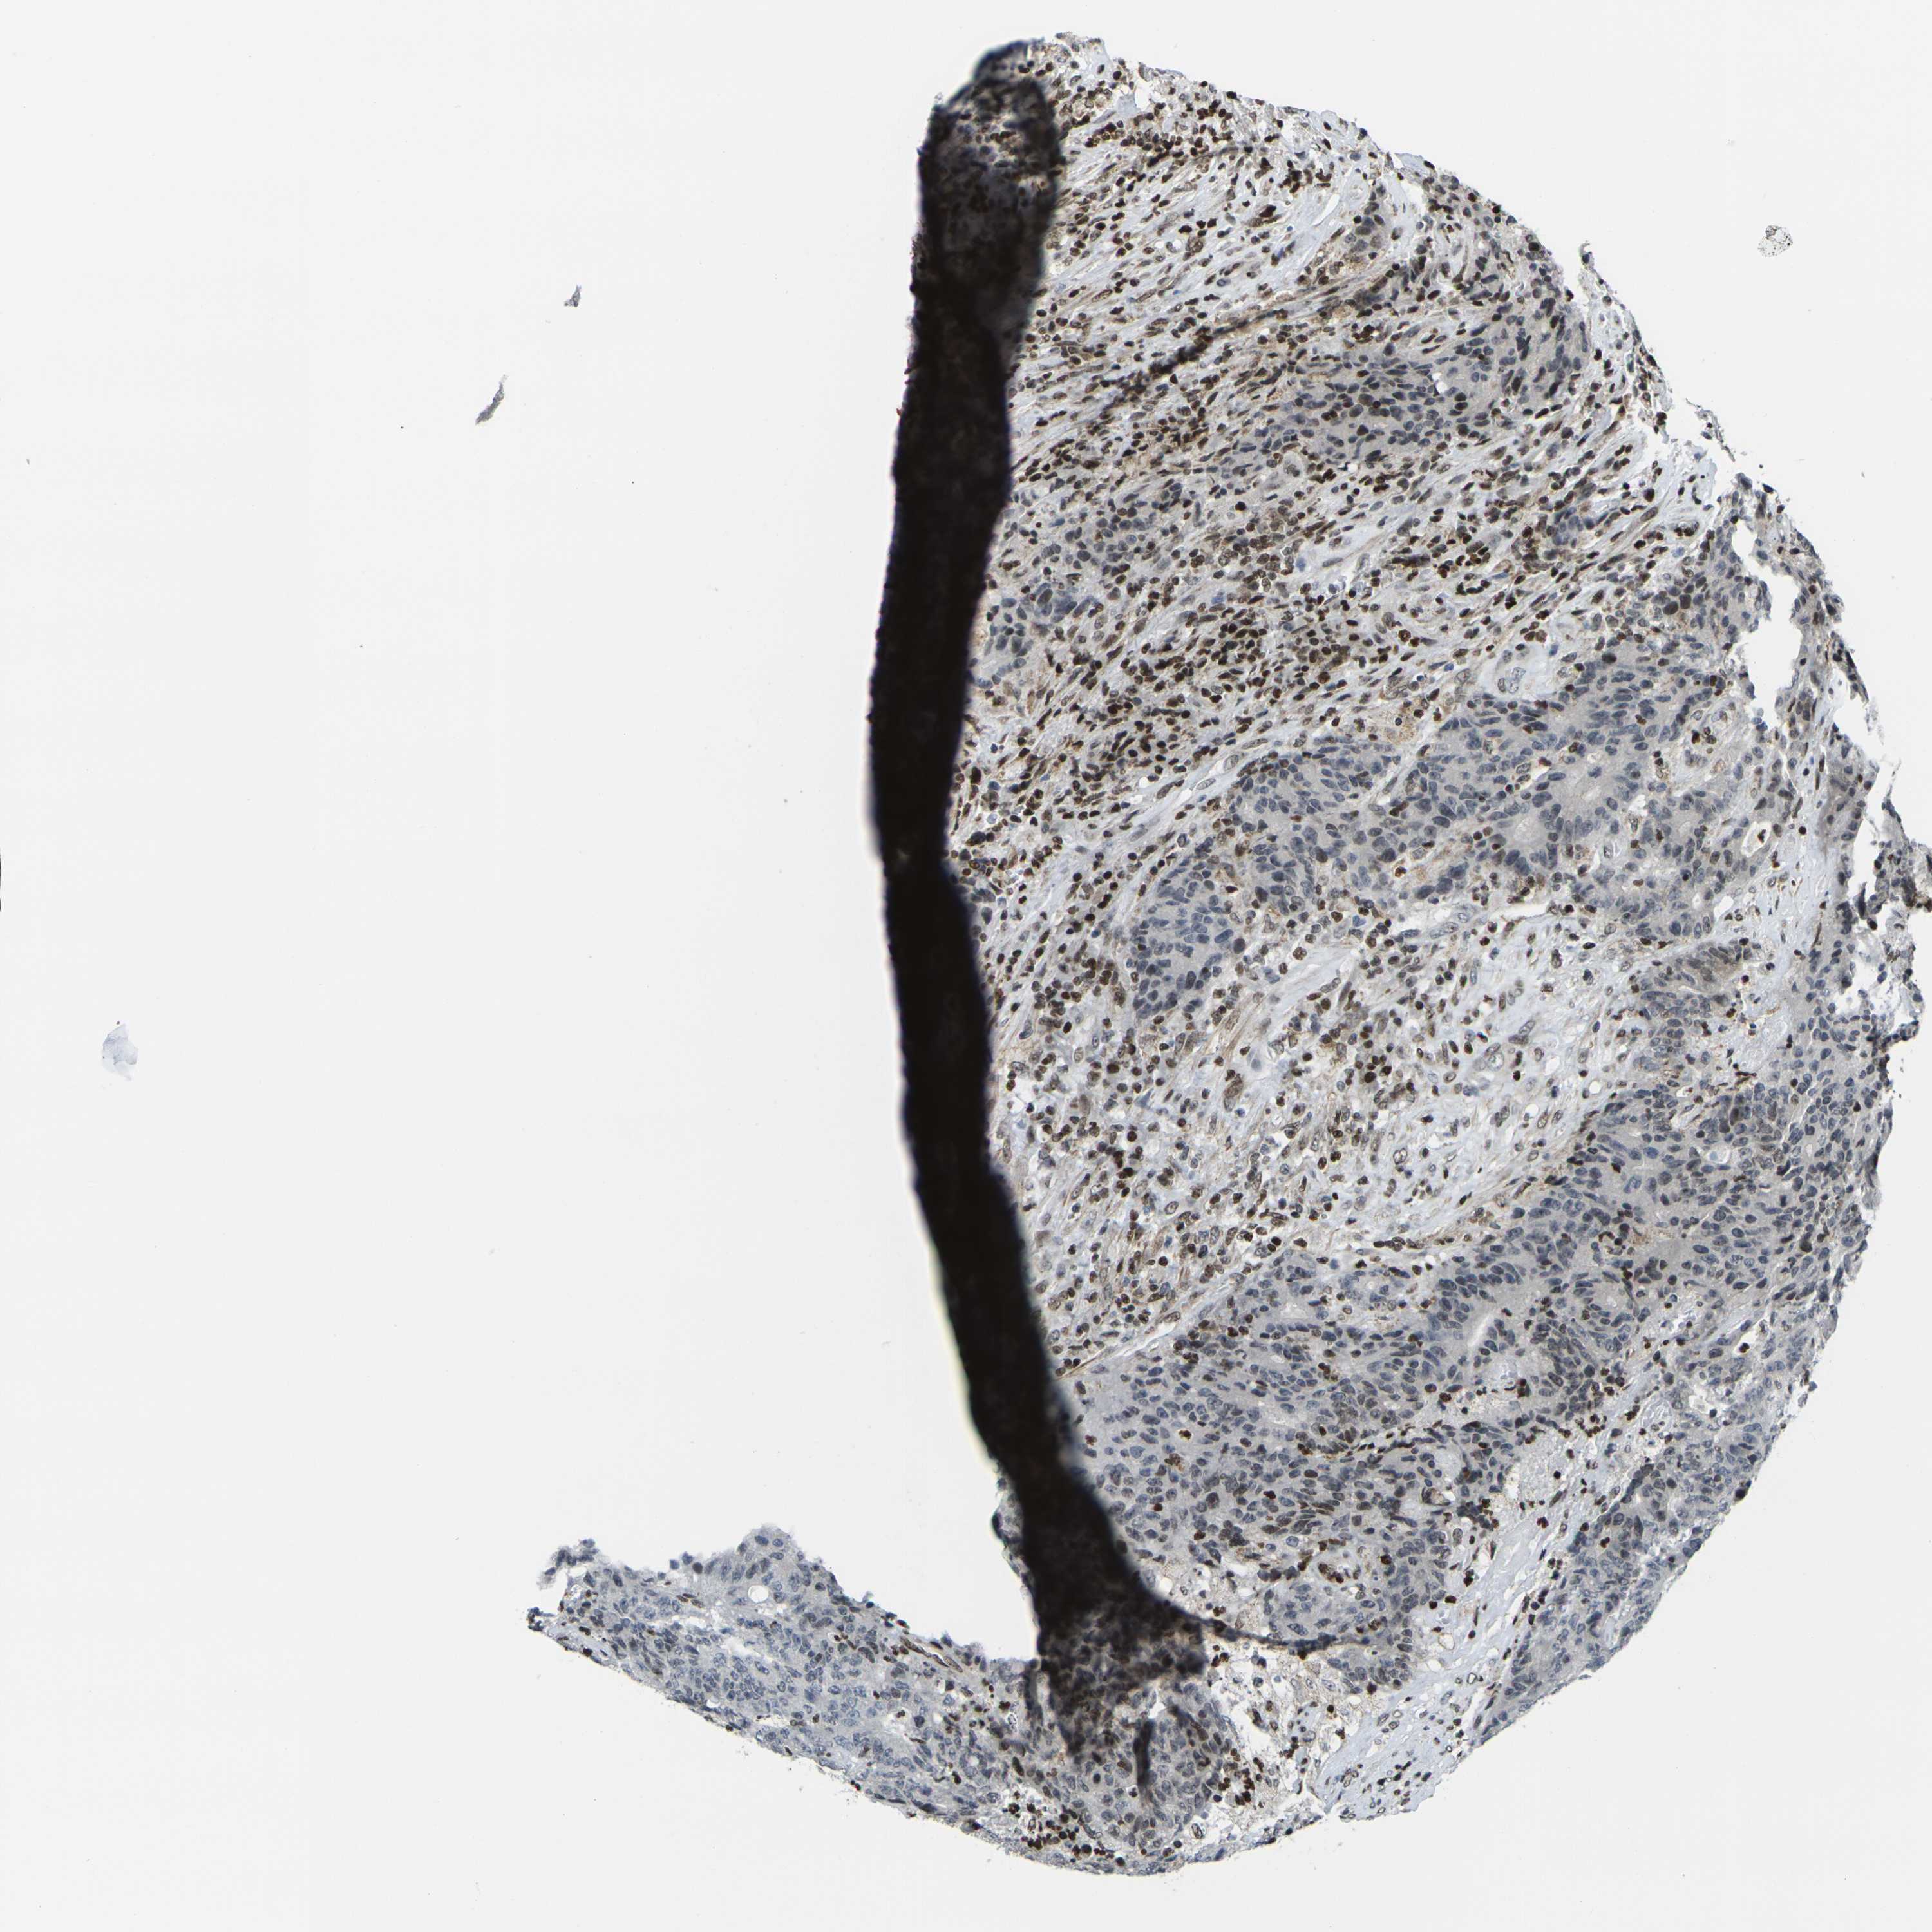

CANCER COLORECTAL CANCER Show tissue menu

Colorectal cancer

Human cancer

Colon adenocarcinoma